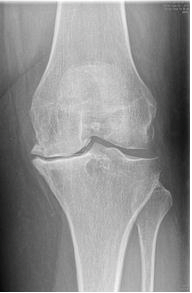

Door de slijtage(artrose) van uw knie is het kraakbeen van zowel het bovenbeen, het onderbeen als de knieschijf verdwenen. Hierdoor schuurt het bot van het bovenbeen, het onderbeen en de knieschijf tegen elkaar. Dit veroorzaakt pijn.

Bij het plaatsen van een totale knieprothese worden deze oppervlakken opnieuw bekleed (met metaal en plastiek). Deze materialen glijden bijna even goed als kraakbeen en zijn zeer slijtvast. De materialen zijn zo gekozen dat het lichaam ze goed verdraagt (en er dus geen afstotingsverschijnselen optreden).